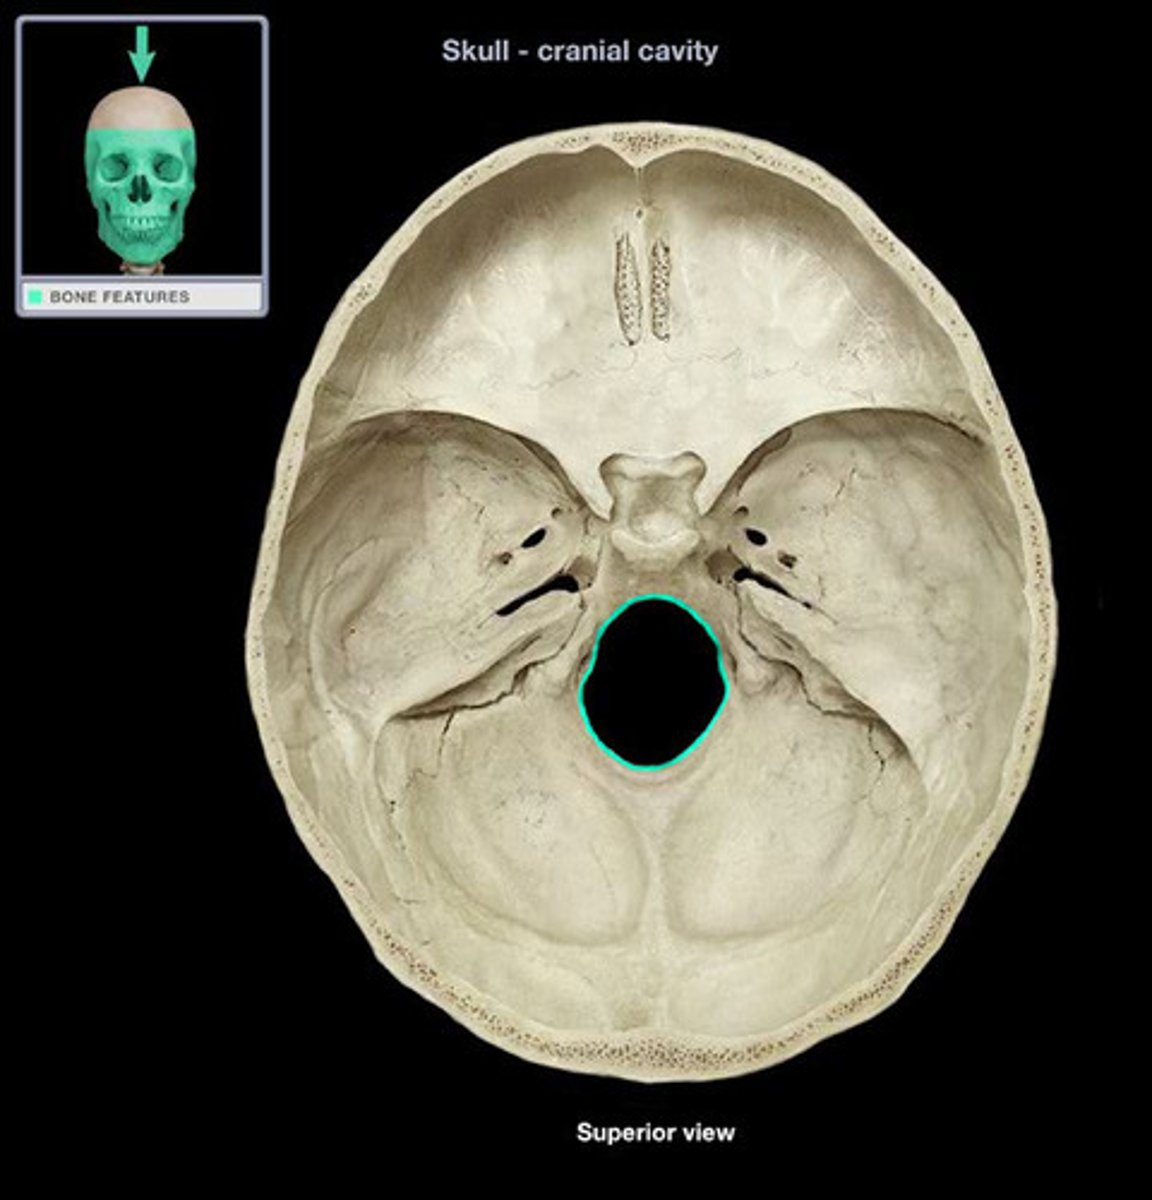

Foramen magnum

Cribiform plate

Sella turcia (hypophyseal fossa)

Foramen ovale

Greater wings

Less wings